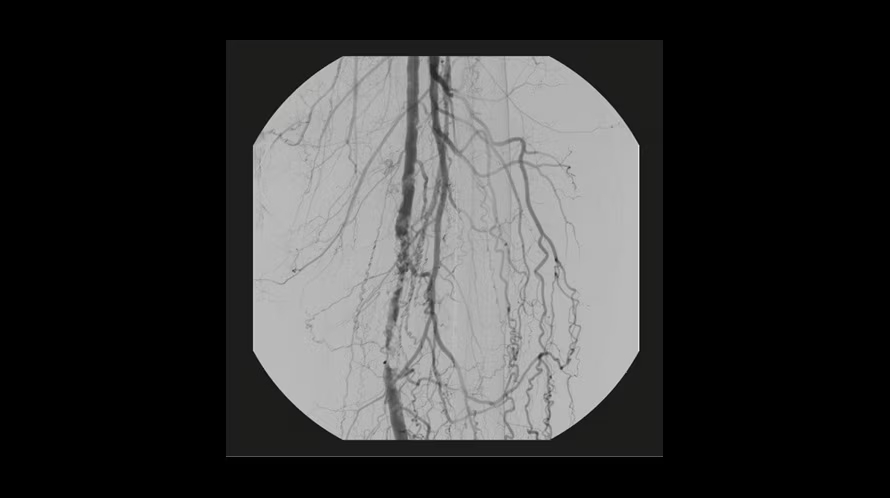

GE OEC Elite CFD относится к мобильным рентгенохирургическим системам премиум-уровня и предназначена для проведения интраоперационных рентгеноскопических и рентгенографических исследований в хирургии, травматологии, ортопедии, сосудистых и эндоваскулярных вмешательствах, нейрохирургии и урологии. Плоскопанельный КМОП-детектор с полем обзора 21×21 см, высоким динамическим диапазоном и частотой до 30 кадров/с обеспечивает детализированную визуализацию костных структур, мягких тканей и контрастированных сосудов в режиме реального времени. Передача изображения 1:1 на 32-дюймовый 4K-монитор просмотровой станции позволяет хирургу уверенно ориентироваться в операционном поле, контролировать положение инструментов и имплантов, минимизируя количество повторных экспозиций.

| Цифровая рентгенография / Cine | Регистрация последовательности кадров с высокой частотой для анализа динамики контрастирования и движений. |

| Цифровая субтракционная ангиография (DSA) | Вычитание фоновых структур для повышения видимости сосудистого русла при контрастных исследованиях. |

| Сосудистые и навигационные режимы | Специализированные профили (Vascular, Cardiac, Roadmapping) для визуализации сосудов и навигации проводников. |